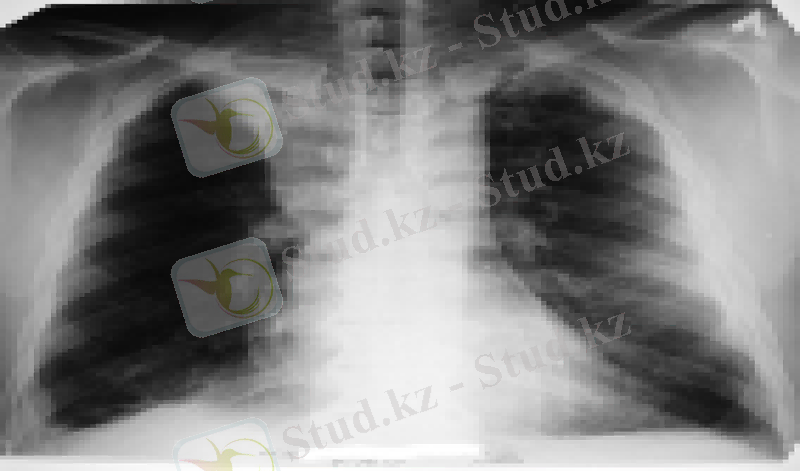

Дәрігер практикасында жиі кездесетін кпе мөлдірлігін синдромында созылмалы өкпе эмфиземасы жиі кездеседі. Эмфиземе жиі біріншілік ауру болады. Ол бронхтардың зақымдауында кездеседі, бұл жағдай атрофияға және өкпенің эластикалық тінің төмендеуінде, қан құйылуының төмедеуінде кездеседі және бұл өкпе клемінің үлкеюіне әкеледі.

Шектеулі мөлдірлеу синдромы- өкпе аймағының жергілікті жоғары деңгейінде ағаруымен сипатталады. Ол сақиналы немесе бұрыс кескін түрде болады. Өкпеішілік бөлігінің мөлдірлігі шынайы және жалған өсінділерде, кистоздық гипоплазияда, абцестерде, туберкулездің деструктивтті кескінде, перифериялық ісіктерде кездеседі.

Өкпе сыртылық млдірлік синдромы шектелген пневмоторакста, диафграмальдық грыжаларда айқын өзінің кескін бейнесін береді. Ол кпенің әртүрлі патологиялық өзгерістерді тудырады: туа біткен дефармация, ісіктерде, қабыну процестерінде кездеседі.